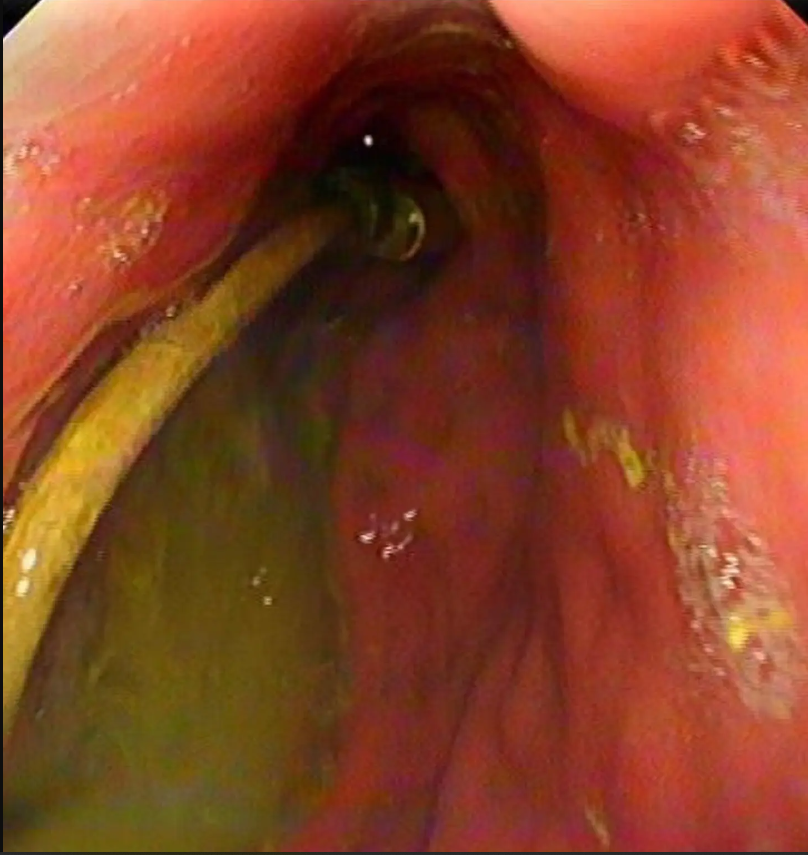

Туркийн Диарбакир хотын иргэн 15 настай хүүгийн гэр бүлийнхэн хүүгийн дотор муухайрч, гэдэс нь өвдөж байгаа гэх шинж тэмдэгтэйгээр яаралтай тусламжийн төвд иржээ. Хүүг тэр даруйд нь рентгенд харуулахад эмч нар цочирдмоор зүйл олж харжээ. Хүүгийн гэдсэнд USB кабель гацсан байсан бөгөөд нэг үзүүр нь нарийн гэдсийг нь цоолсон байв.

Эмч нар яаралтай дурангийн хагалгаа хийн 91см-ийн урттай кабель хүүгийн гэдэснээс гаргаж авсан бөгөөд энэ үеэр үсний боолт мөн гарч ирсэн байна.